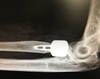

Qual o nome e pra que serve essa incidência ?

Incidência oblíqua apical de GARTH > avaliar HILL SACHS

Para que serve essa incidência ?

Avaliar BANKART + HILL SACHS

Que incidência e essa é pra que ?

Striker >Avaliar HILL SACHS